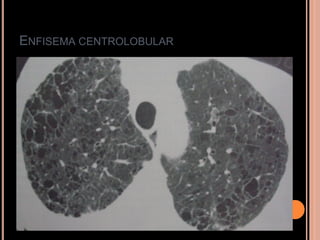

ENFISEMA CENTROLOBULAR

   Múltiplas áreas redondas de atenuação

anormalmente baixas ( mais em LS);

   Áreas de radiotransparência geralmente próximas

ao centro dos lóbulos pulmonares envolvendo os

ramos das artérias centrolobulares;

Eventualmente podem ser vistas paredes finas

relacionadas à fibrose adjacente;

Mais grave  confluência  enfisema centrolobular

confluente (simula enfisema panlobular);